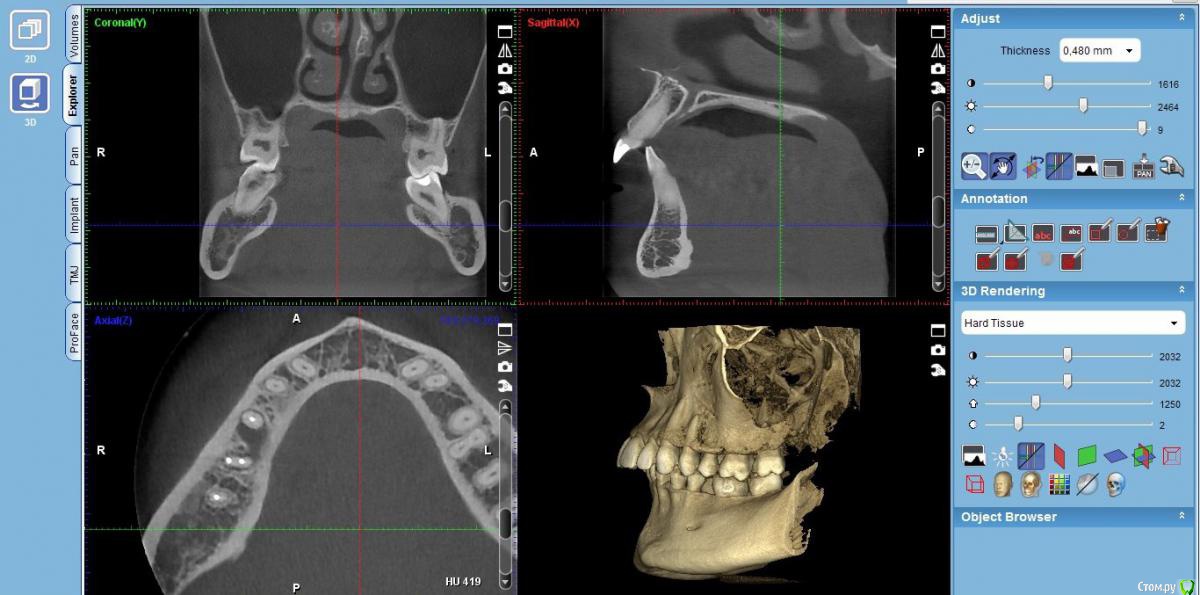

Volha Опубликовано 27 сентября, 2017 Поделиться Опубликовано 27 сентября, 2017 Посоветуйте, что делать с зубами. Здравствуйте!Нужна помощь. После лечения пульпита у премоляра, появился гнойник на десне (с внутренней стороны). На последнем сделанном снимке, помимо имеющегося воспаления, видно воспаление у корней 47 зуба. Врач предположил, что это все может быть трещина корня и нужно перелечивать все каналы под микроскопом. При этом нет никаких гарантий что это поможет. Есть вероятность того, что после всего проделанного лечения эти зубы придется удалять. Может есть другой вариант как это исправить? Судя по ценам, как я понимаю, выдернуть эти зубы и вставить импланты выйдет не слишком дороже лечения. P.s Посмотрев снимки, увидела что у меня действительно "убогий прикус" =). Буду признательна советам как это можно исправить. Ссылка на комментарий

DmitrySH Опубликовано 28 сентября, 2017 Поделиться Опубликовано 28 сентября, 2017 видно воспаление у корней 47 зуба. Нет. Только 45,46 Ссылка на комментарий

Volha Опубликовано 28 сентября, 2017 Автор Поделиться Опубликовано 28 сентября, 2017 Нет. Только 45,46 Не исключаю, что могла перепутать. Два рядом стоящих зуба, маляр и премоляр. Ссылка на комментарий